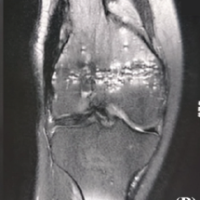

The patient returned to the ED with increased pain and purulent drainage (Fig. 5). She remained pancytopenic with platelets of 59, hemoglobin of 8.7, and elevated coagulation laboratories. The orthopedic team recommended a formal right hip I&D.

Figure 5: Anterior-posterior X-ray of the right hip upon readmission before second incision and drainage. Note the sharp spike of the greater trochanter.